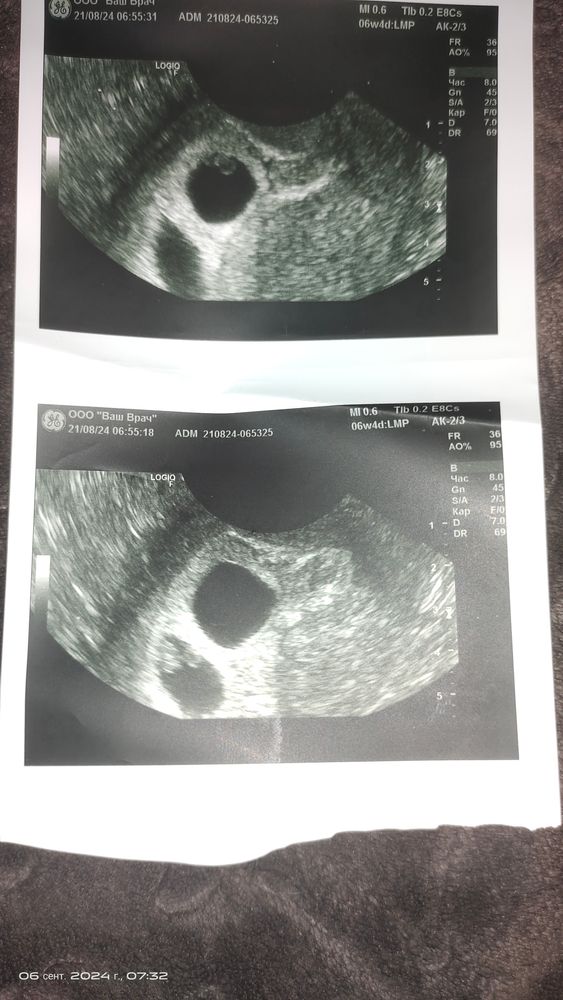

6 недель моно ди Изображение

Как кружочки

На вашем снимке похоже на моно ди . Одно пя и два жм( плода?)

06.09.2024